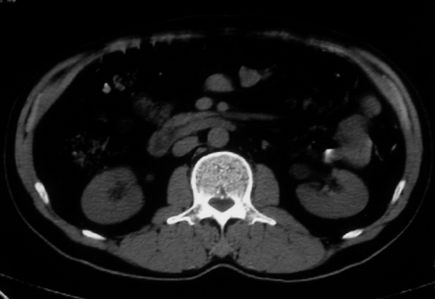

男,体查发现右肝低密度,右肾高密度结节影。高密度ct值92hu,囊肿?

肝右叶囊肿或血管瘤?右肾高密度囊肿。建议增强。

肝右叶圆形低密度灶,考虑囊肿或血管瘤,建议ct增强检查;右肾包膜下高密度圆形灶,考虑:囊肿并出血